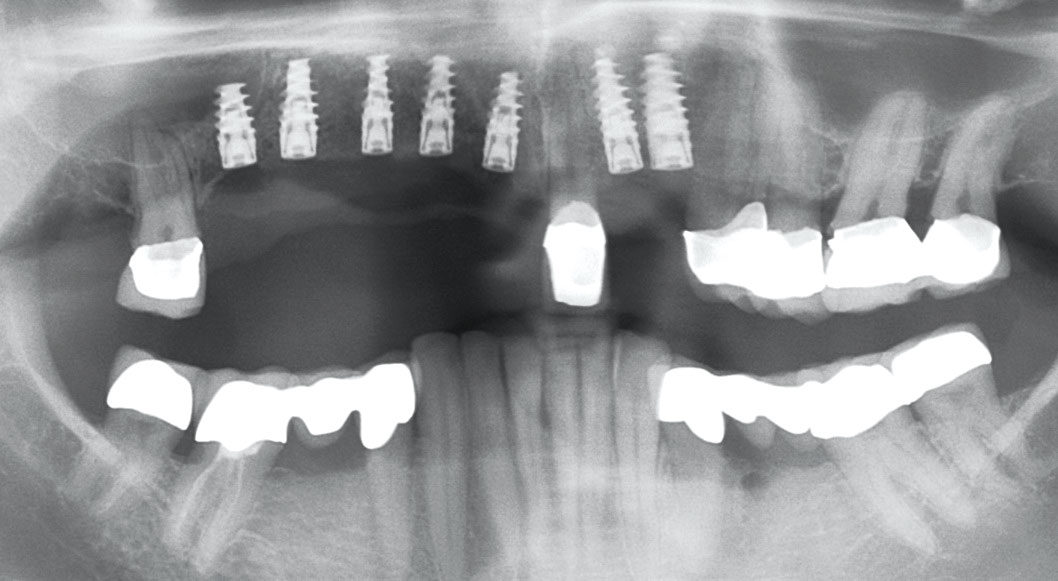

Full maxillary reconstruction with maxgraft® bonebuilder - Dr. C. Hilscher

Initial x-ray, ten years post implantationem alio loco, large peri-implant bone loss